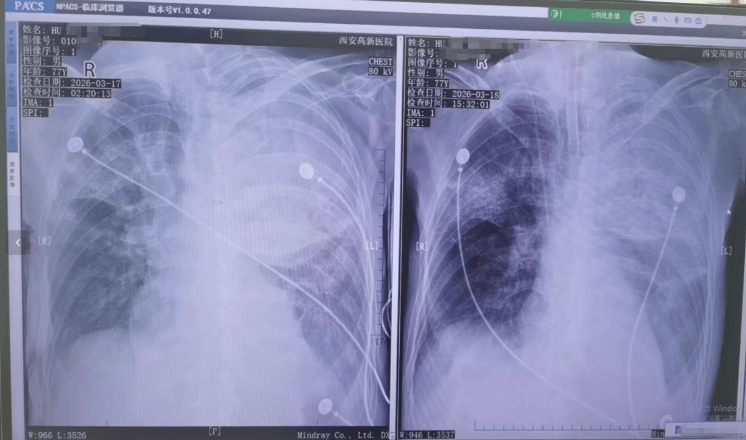

▲患者接受转院治疗

胡先生说,起初以为是感冒,住院治疗没有效果,还越来越严重,以至于病情危重,“整个肺部全白了”,并且出现呼吸衰竭,医院甚至下了病危通知书世界杯真钱开户 。3月17日,家人赶紧将父亲转院到西安高新医院抢救,到医院以后就住进了ICU。经检查,才发现是鹦鹉热衣原体感染导致的重症肺炎。胡先生提供的一份《西安高新医院诊断证明》显示,胡先生的父亲3月17日以重度肺炎入院。诊断为重症肺炎(鹦鹉热衣原体感染)I型呼吸衰竭,急性呼吸窘迫综合征,脓毒症等。

▲患者胸片